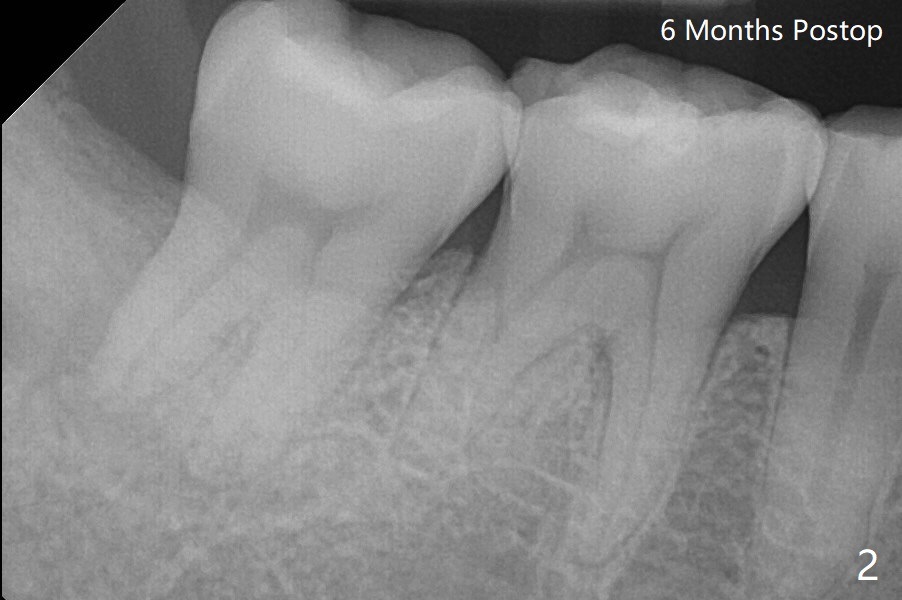

A 44-year-old woman agrees to have #32 extraction to alleviate #31 distal bone loss (Fig.1).  IANB, hockey-stick incision made, reflected mucoperiosteal flap, buccodistal trough, sectioned for multiple times, straight elevator/forceps removal, curette to remove tooth bud sac, copious irrigation, IA neurovascular bundle partially exposed, intact, + hemorrhage, packed with 1 piece of CollaForm plug and 1 and 1/2 Osteogen plug and Vanilla Cancellous/Cortical Mix in the socket, latter was washed out by bleeding, 4-0 plain gut suture, 2x2 gauze, hemostatic, watched in office for 1/2 hour, changed gauze once, hemostatic, bite block used during ext. Pt was doing fine, satisfied and with good anesthesia. Oral/written POI and extra gauze given. Amoxicillin, Medrol dose pak, Tylenol III, Called pt by the evening. She has mild pain in throat and mild swelling. Sensation returns. There is no hemorrhage.  Six days postop, "pain is being reduced".  There is light R facial swelling and localized induration.  No erythema is observed in the extraction site.  Six months postop, the tooth #31 has mobility I/II (Fig.2).  The patient can chew with it and is satisfied.  One year postop, "LR tooth loose. I dare not to use it". There is no BOP including #31 with mobility II.  There is bone regeneration at #32 socket 2 years 9 months postop (Fig.3).